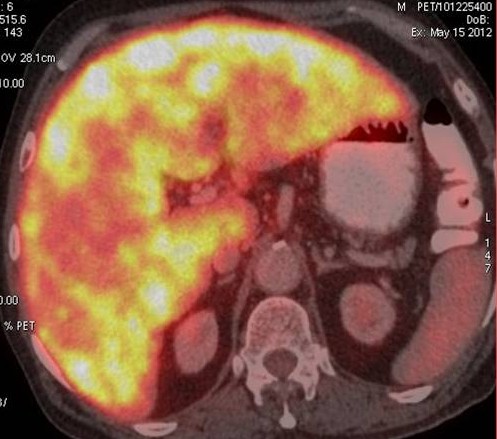

CT scan of the abdomen confirmed the findings ; For further clarification PET whole body scan was done at a centre in Chennai. The following images are from that.

Extensive FDG avid hepatic metastases involving both lobes.